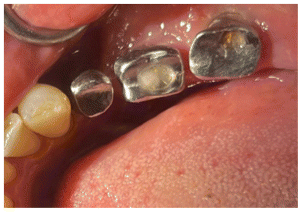

Four months later, the implants were discovered and the healing caps were placed, in the second molar, a custom provisional was made for each restoratio to establick the counter and emergence profile of the crown (Figs. 28, 29, 30).

An analog conventional open tray impression was taken with polyvinyl siloxane to obtain the implant model because the tissue depth did not allow us to perform a good scan of the area.

Due to the angulation of the crowns individual milled abutments were fabricated to correct the angulation and achieve a better occlusion with porcelain-fused-to-metal crowns. (Figures 31, 32).

The first premolar due to the inclination had to be milled and a cemente Crown was used, the mollars were milled and scre retained (Figure 33).

The abutments were torqued to 30 Newtons. The premolar crown was cemented with Premier implant cement, and the screw access channels of the molar crowns were filled with resin (Figs. 34, 35).